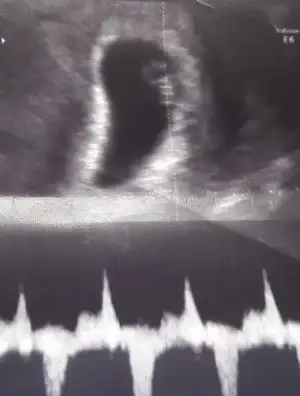

Merhabalar, Doktordan çıktım kızlar. Normalde 11 hafta 5 günlük ama ultrasonda 12 hafta 2 günlük çıktı bebeğim. Ensesi 1,5 mm çıktı. Elini kolunu sallıyordu pek tatlıydı ağlayacaktım duygulandım. Burnuşunu gördüm. Hele bi doğsun öpeceğim o burnuşunu. :) kan sonucum 1 hafta sonra çıkıcakmış. Sonucu eşim gösterecek. Bana da 5 hafta sonra gel dedi sorun çıkmazsa(inşallah çıkmaz) yuzde 51 erkek dedi :) ama kabullenmedim oran düşük çünkü. Bi dahaki kontrolde net söylerim dedi. Darısu diğer 2li teste girecek annelere.